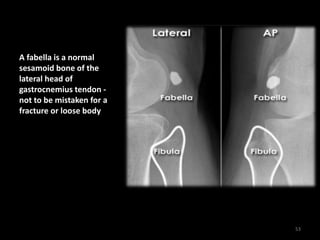

Knee - Fabella

52

A fabella is a normal

sesamoid bone of the

lateral head of

gastrocnemius tendon -

not to be mistaken for a

fracture or loose body

53